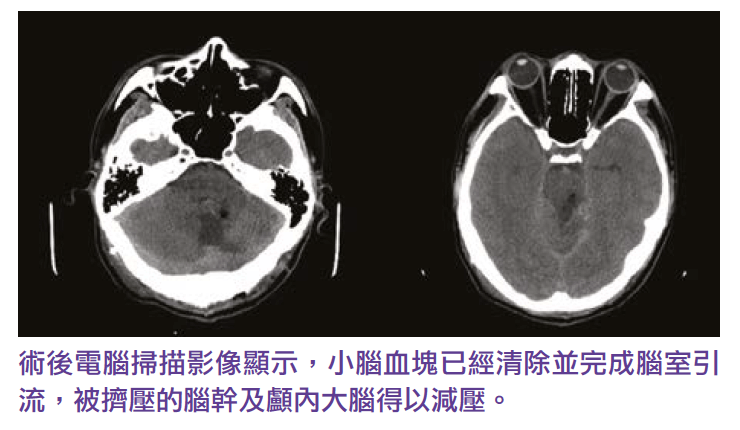

Three years ago, a 46-year-old Ms Leung, has headaches for three or four weeks, consulted his family doctor when arrived at the emergency room, the symptoms disappeared after taking the medication. Later, the brain CT scan report from the public hospital no abnormal finding. so the patient and her family thought that everything was fine. Two weeks later, suddenly felt a severe headache at home and quickly fell unconscious. After emergency treatment in a public hospital, CT scans and cerebral angiography showed that Ms. Leung’s cerebellum had suffered a severe hemorrhagic stroke due to the rupture of a cerebrovascular aneurysm, and that a blood clot in the cerebellum pressed against the brainstem, resulting in hydrocephalus and high intracranial pressure and dilated pupils. A neurosurgeons need to clip the blasted cerebrovascular aneurysm, remove blood clots from the cerebellum, and drain the ventricles through emergency craniotomy to reduce the pressure on the compressed brainstem and intracranial pressure.

After more than three months of intensive treatment and rehabilitation, Ms. Leung was still in a deep coma despite being able to save her life. The doctor told the family that Ms. Leung was likely to become disabled or commonly known as a vegetative stroke survivor in the future, and suggested that the family transfer her to a nursing home and plan long-term care in a private sector after discharge. During staying at the nursing home, Ms. Leung condition did not improve, but also suffer from complications caused by long-term coma and bed resting. In order to get a better chance of recovery, her family transferred her to a private hospital for further stroke rehabilitation. After six weeks of intensive stroke rehabilitation treatments such as drugs, physical therapy, acupuncture, and DC stimulation (transcranial DIRECT current stimulation), Ms Leung finally woke up and regain her speech, can eat and walk. After being discharged from the hospital, Ms. Leung continue to receive medication, physical therapy and brain TMS treatment, and improved swallowing, hand and foot coordination, and walking ability. Three years on, Ms. Leung has not become the vegetative person, but a stroke survivor with mild to moderate disabilities, and she and her family have moved to the UK to enjoy life.